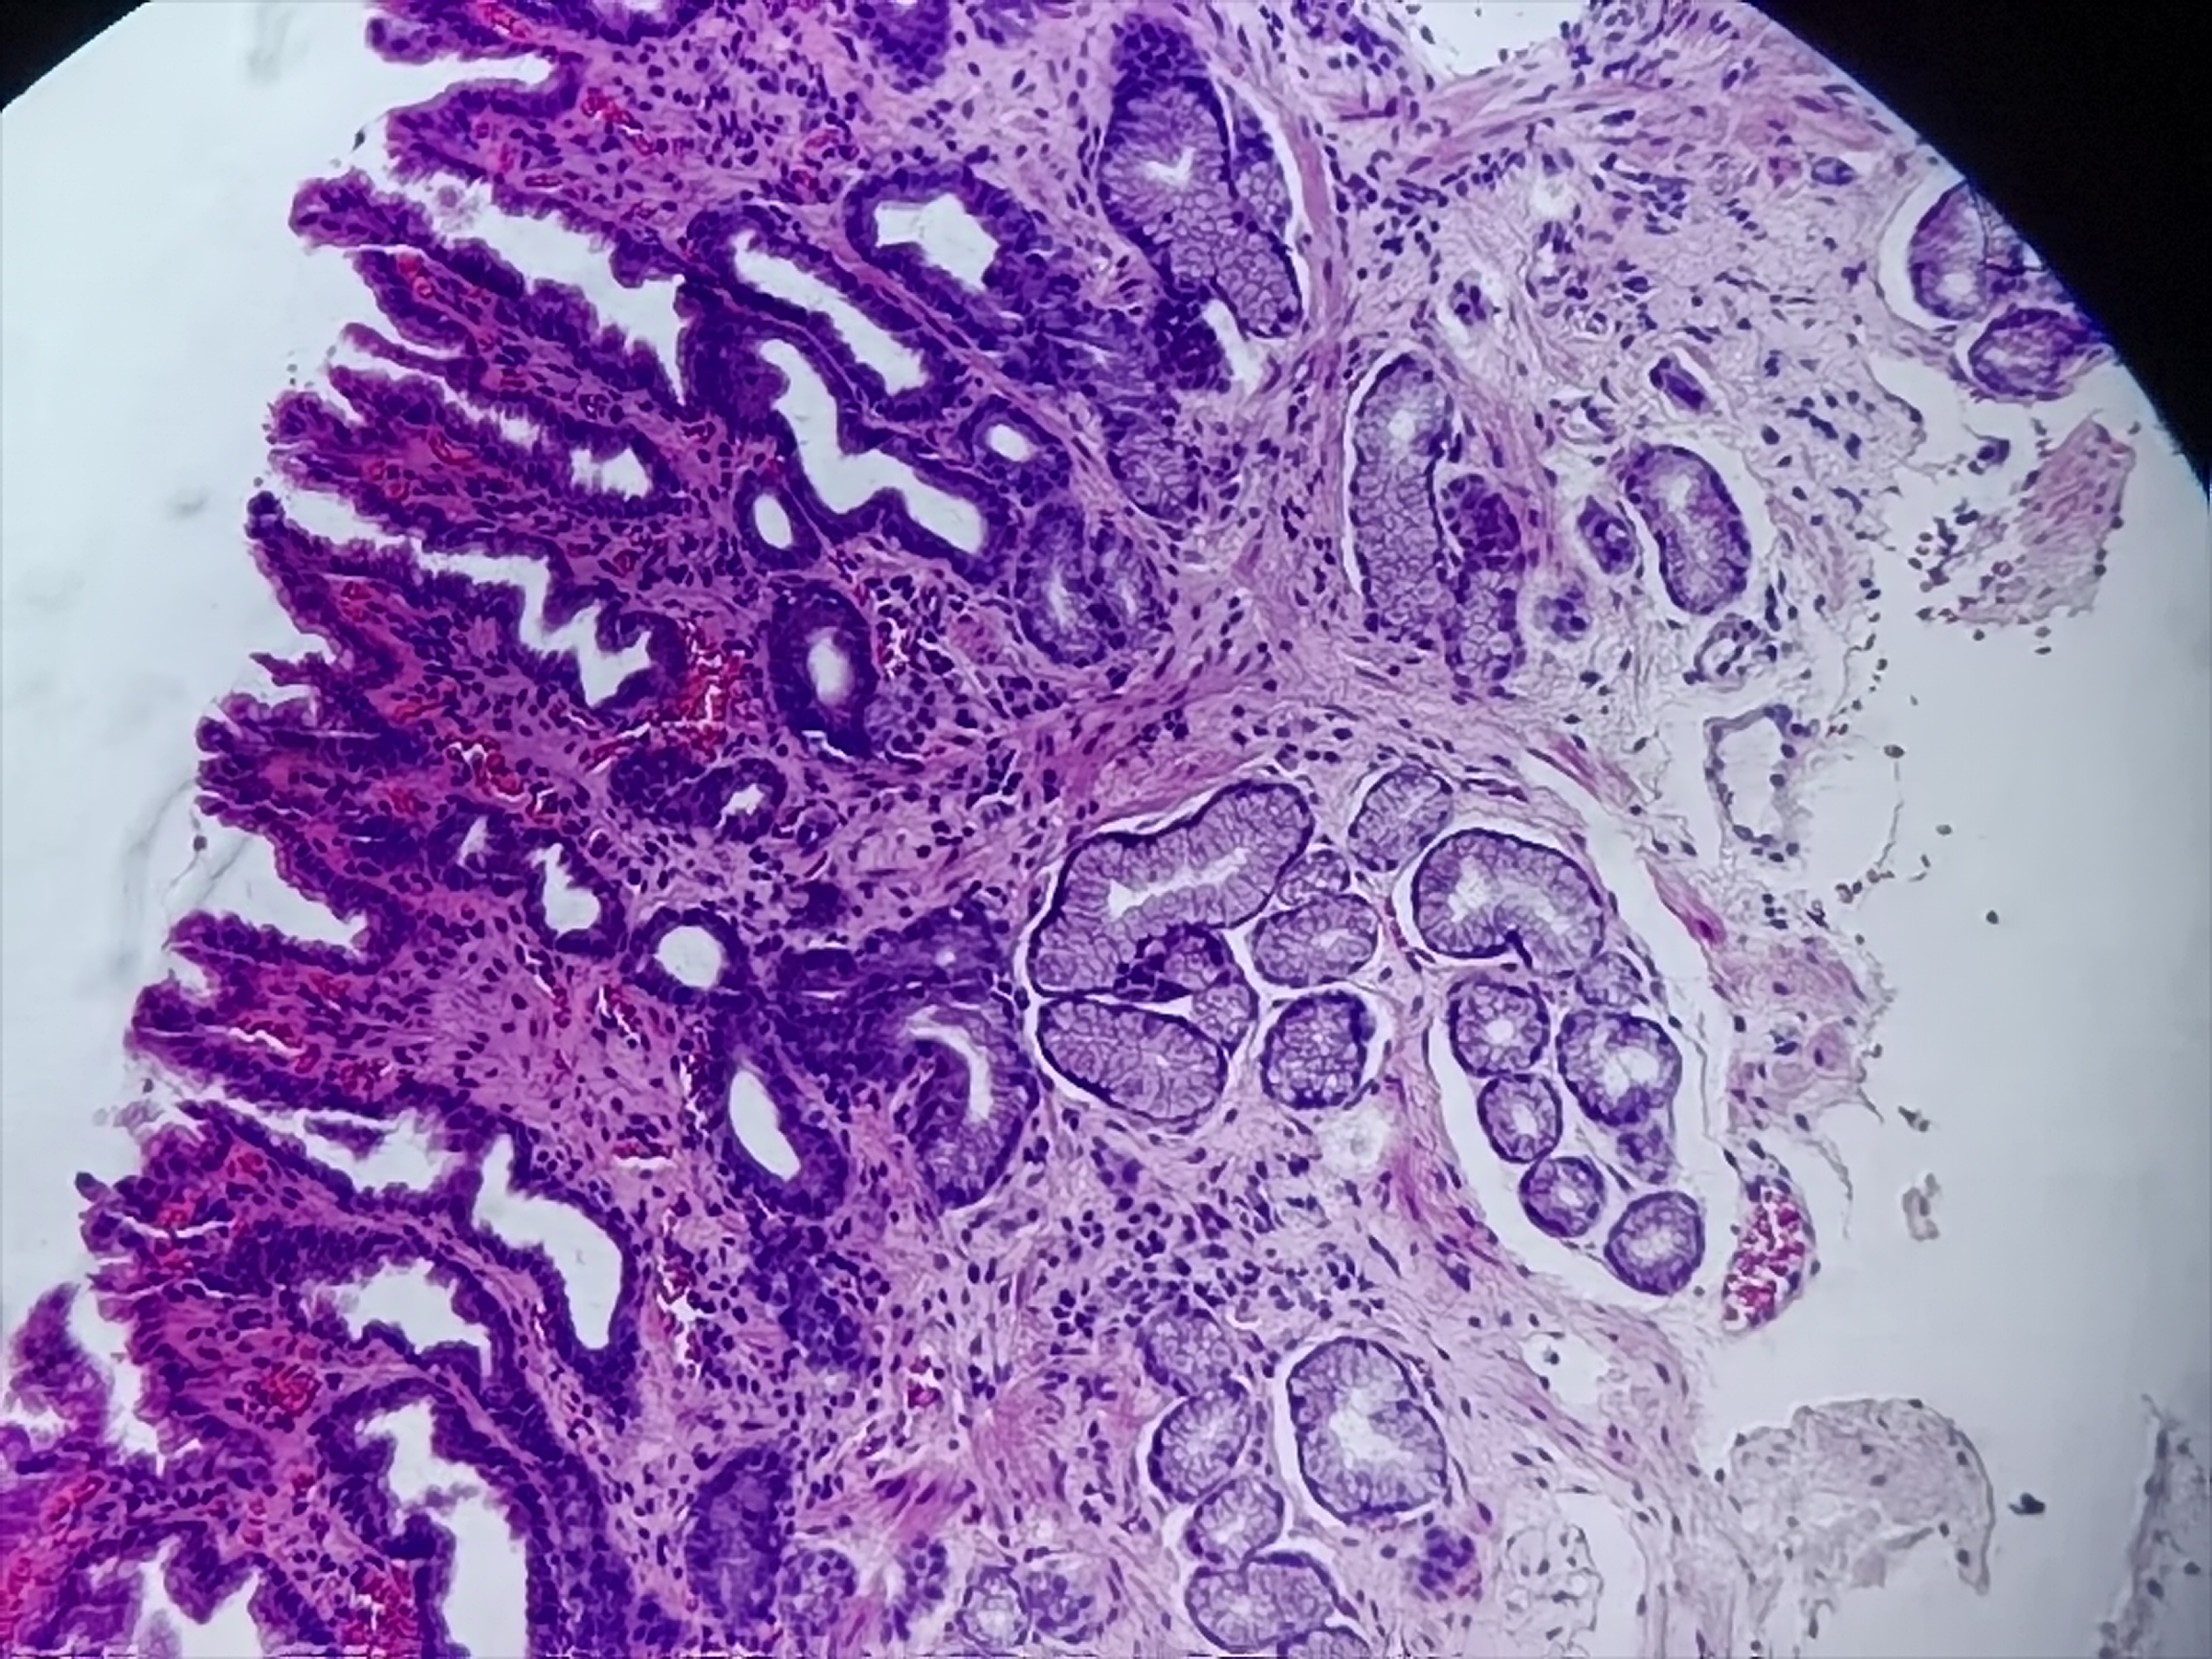

胃活检

1.胃窦:粘膜呈花斑样改变(图1-5);2.贲门:可见一大小约0.4*0.4cm息肉样隆起(图6-15)。

胃粘膜活检

1.灰白色组织1块;2.灰白色组织1块

慢性萎缩性胃炎,增生性息肉